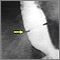

Es un estrechamiento del esófago (el conducto que va de la boca al estómago) que ocasiona dificultad para deglutir.

La dilatación (estiramiento) del esófago es el tratamiento preferido. Usted puede necesitar que le repitan este tratamiento después de un tiempo para evitar que la estenosis se estreche de nuevo.